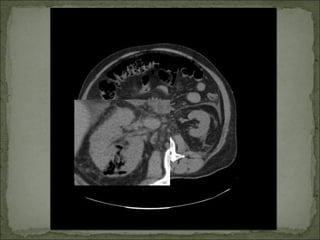

Se solicita TAC abdomino-pélvico.

Sepsis grave de origen urológico: Pielonefritis

enfisematosa.

pronóstico.               TC: método de elección.

Valorado por urología. Sesolicita TAC abdomino-pélvico.

Sepsis grave deorigen urológico: Pielonefritis enfisematosa. Descompensación diabética no cetósica secundaria a Pielonefritis Enfisematosa. Insuficiencia renal aguda secundaria. Celulitis abdominal e inguinoescrotal derecha.